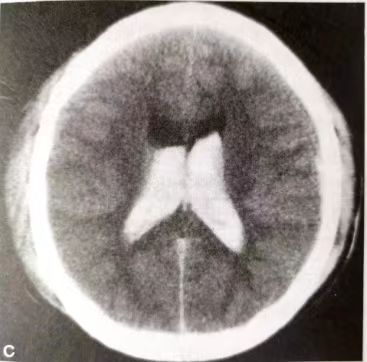

成年患者中出血更常见,约为60%,多数为平时无高血压病史,突然表现为脑室内出血或蛛网膜下腔出血、脑出血等,往往给患者带来严重的神经功能损害。

因此烟雾病分为出血性和缺血性烟雾病两种。